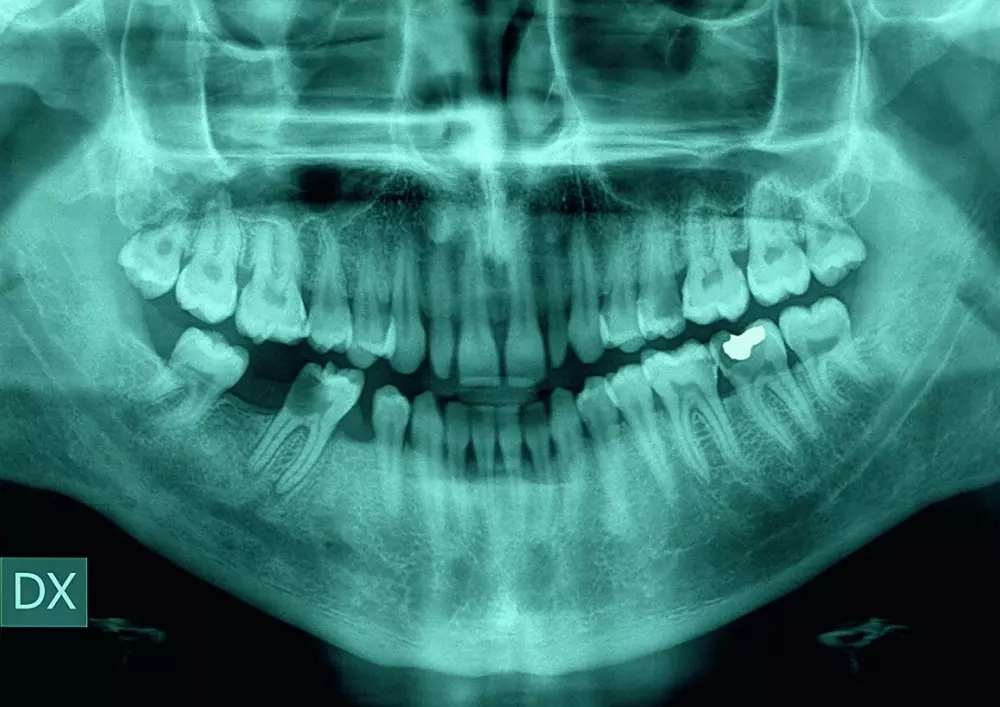

Dr n. med. Beata Walawska pisze, jakie możliwości oferuje współczesna ortodoncja. Podaje, co może wnieść do zespołowego leczenia stomatologicznego. Omawia m.in. ortodoncję profilaktyczną i interceptywną.